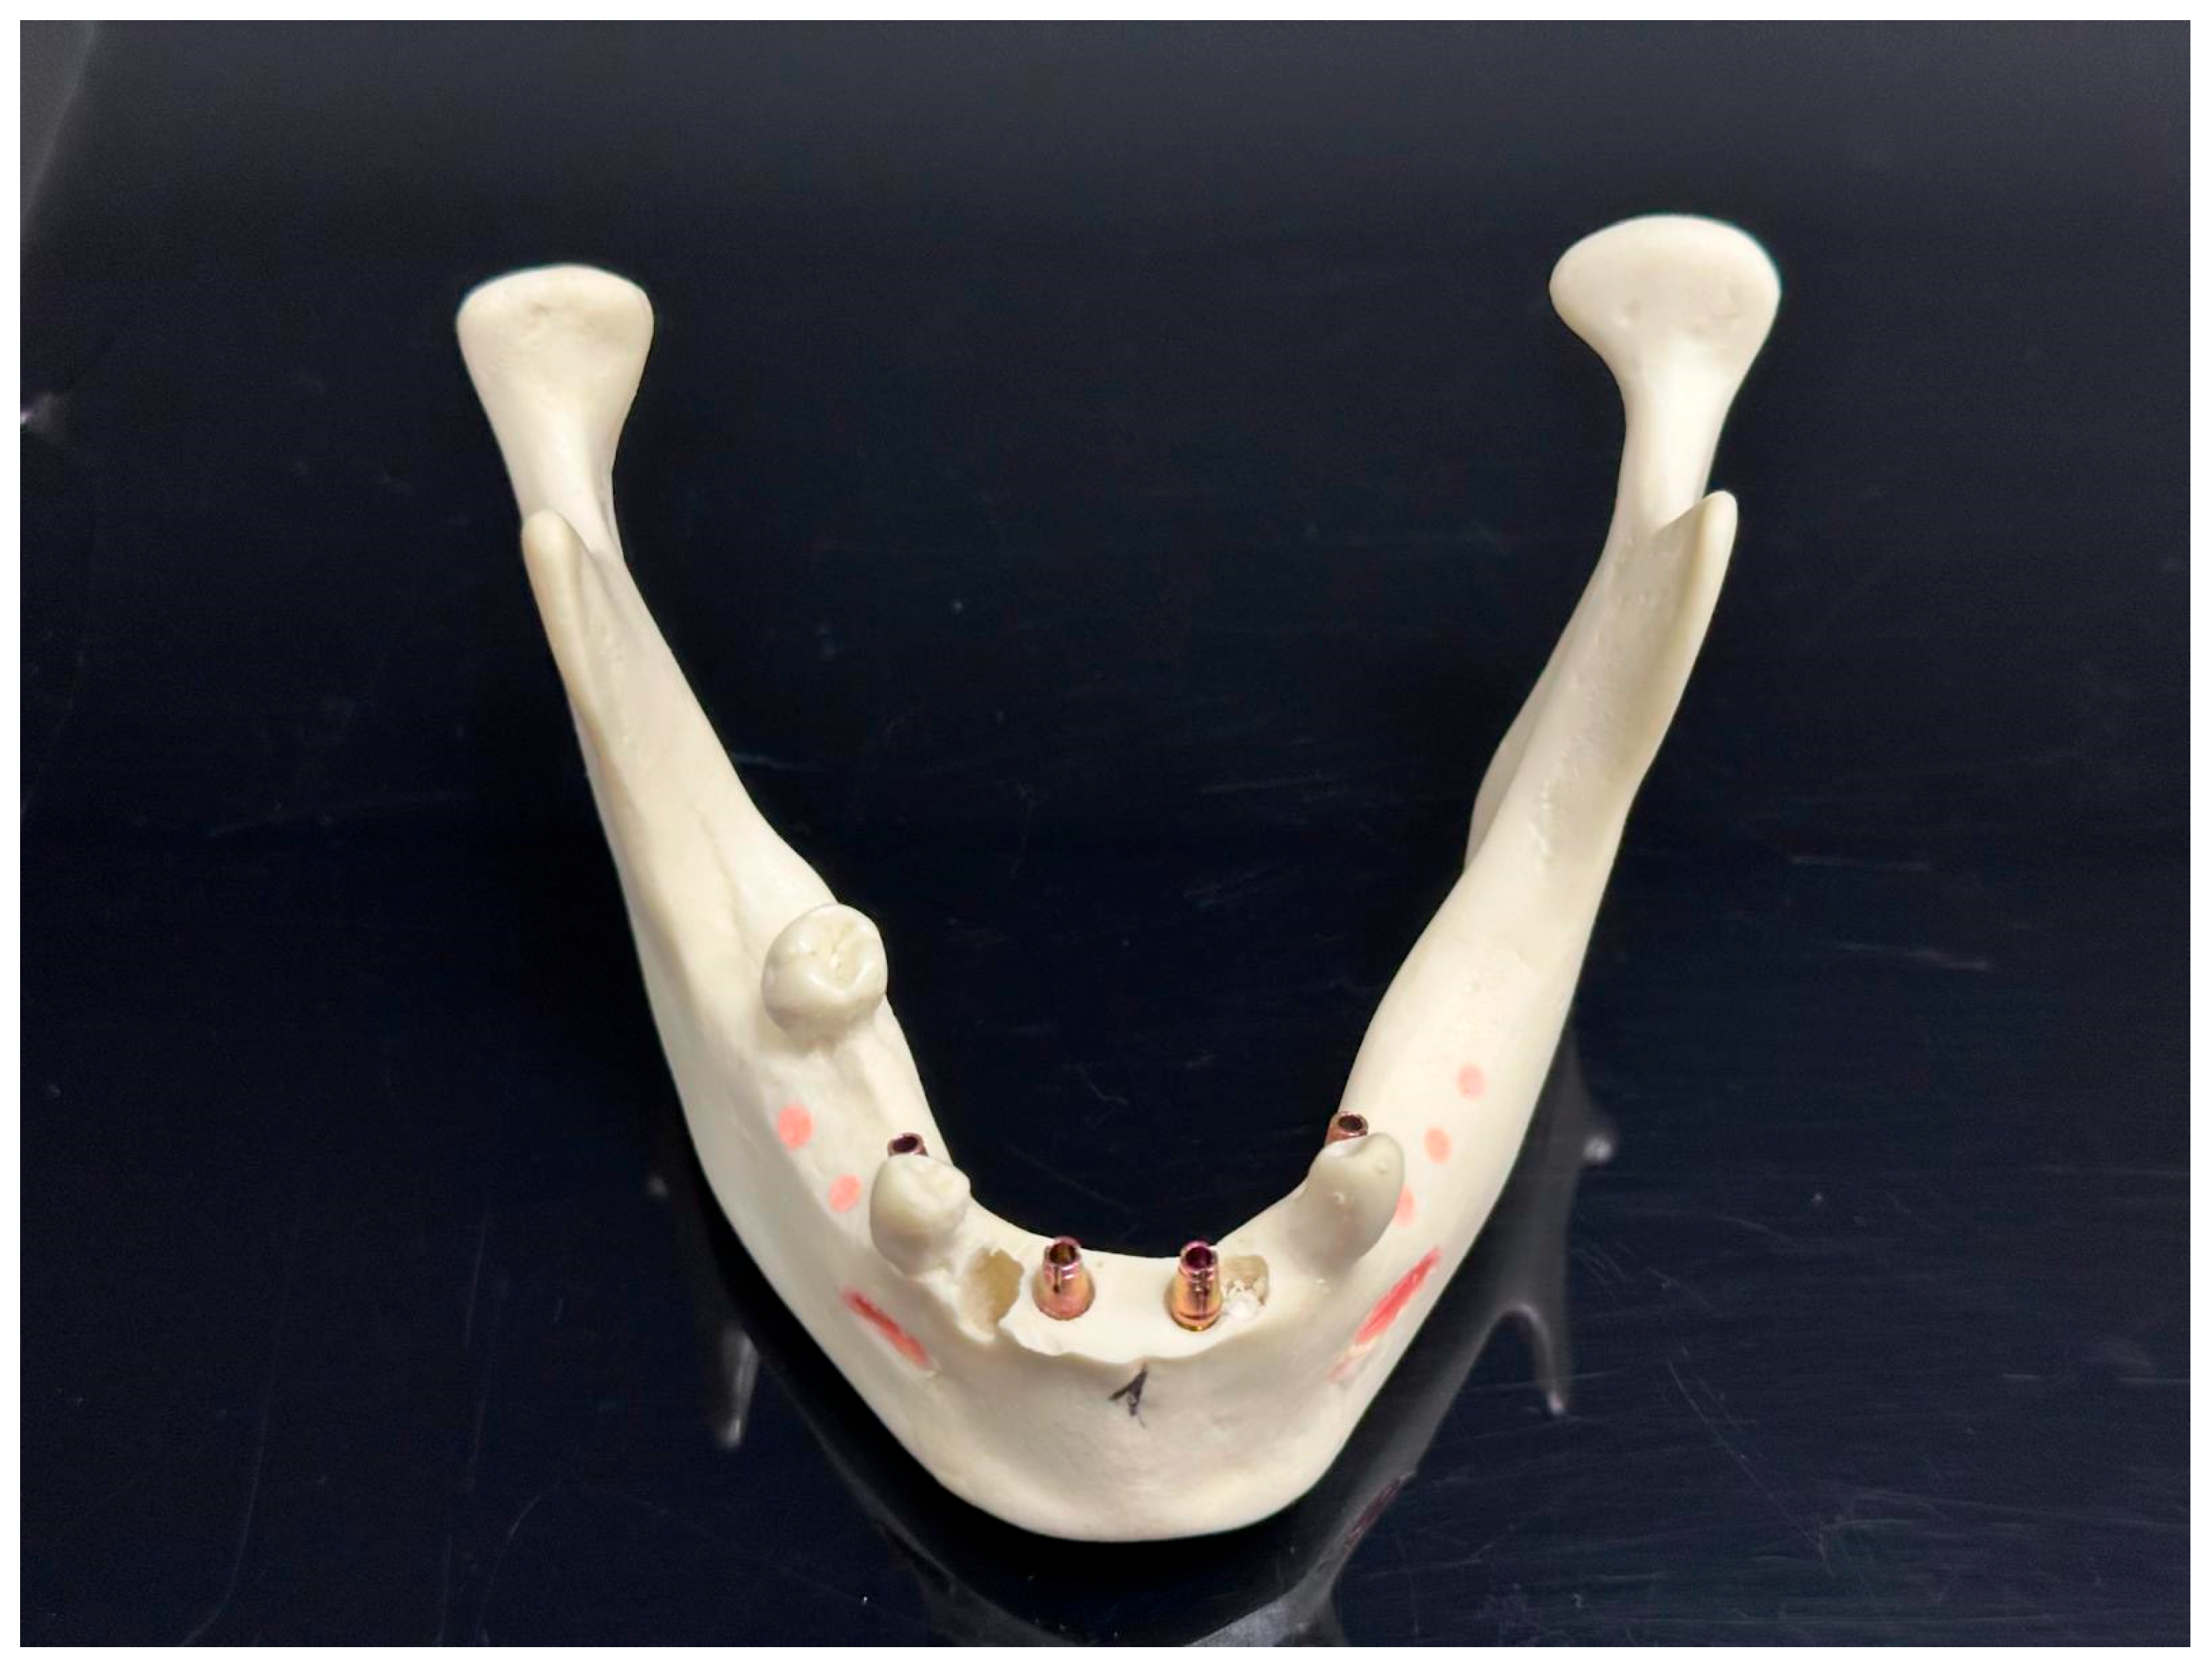

2. Material and Methods